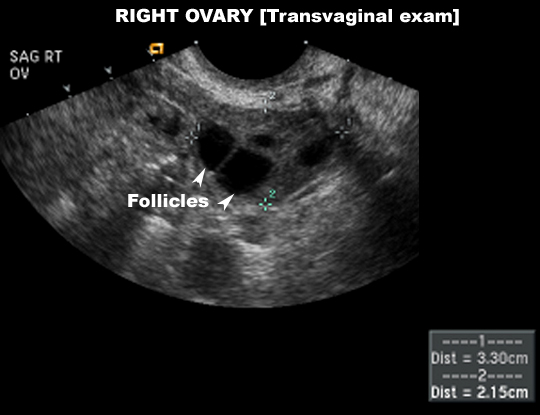

US Pelvis |

|